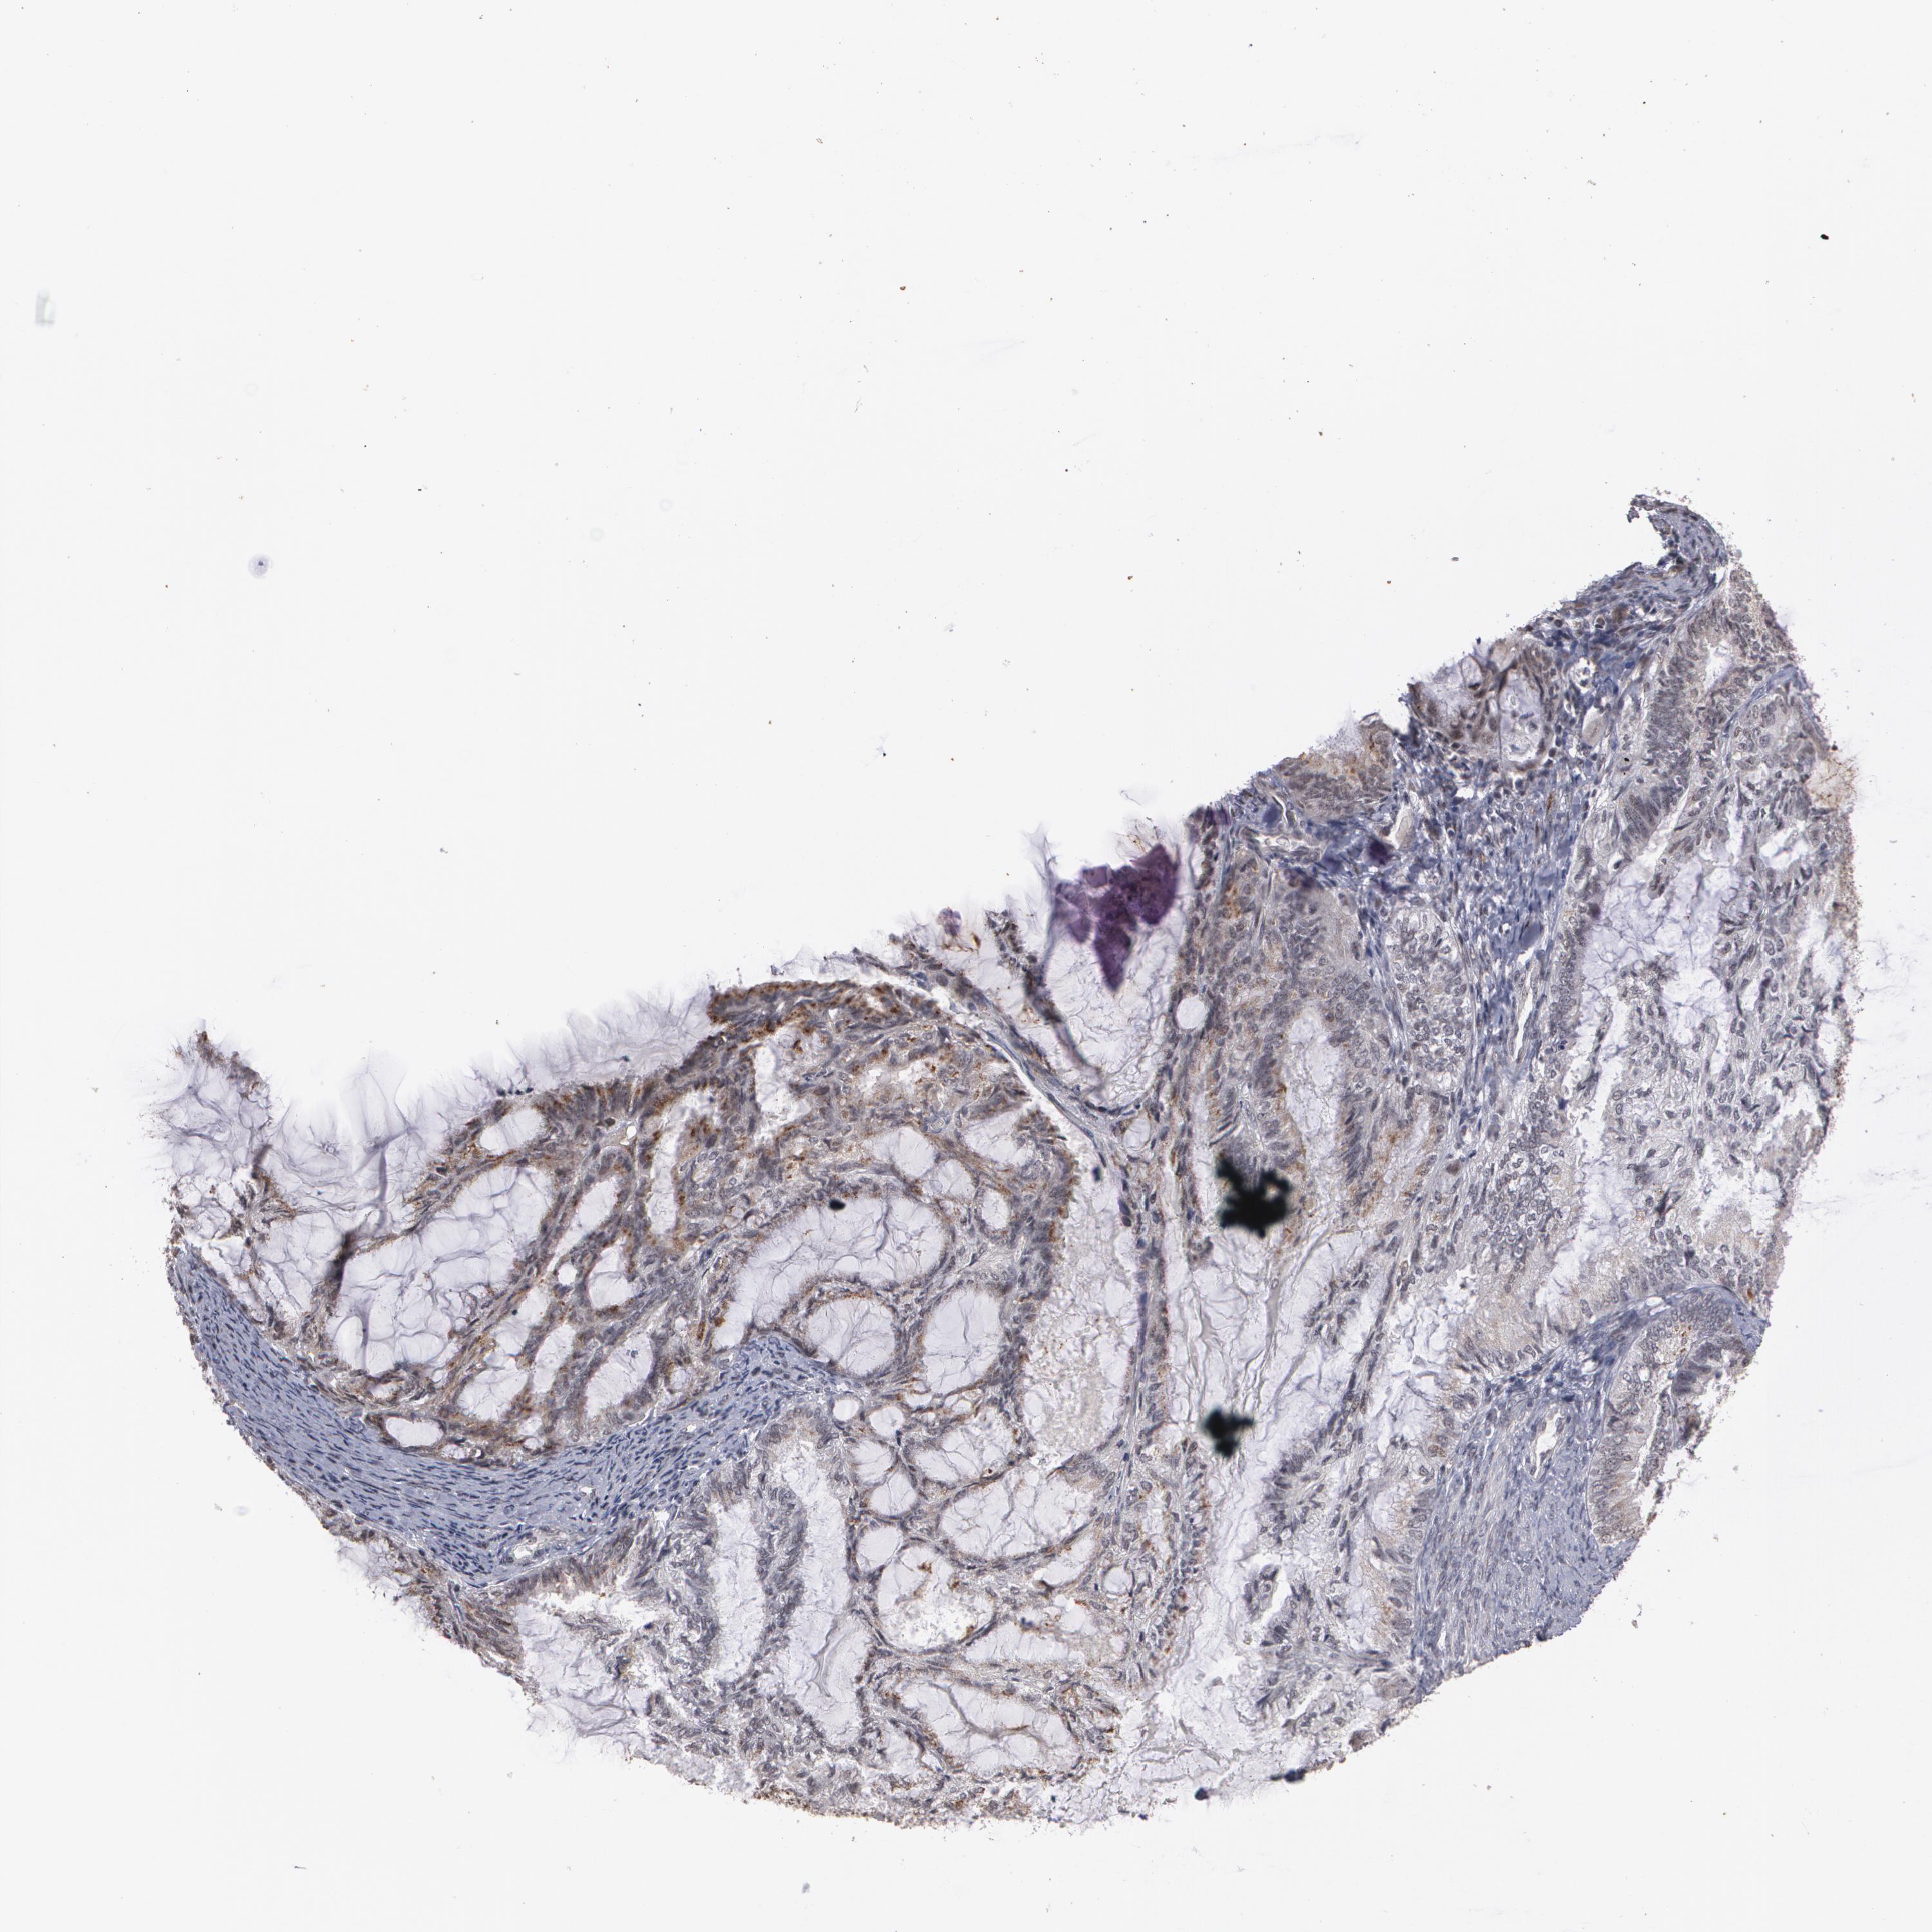

ENDOMETRIAL CANCER - Protein expressioni

A mouse-over function shows sample information and annotation data. Click on an image to view it in a full screen mode. Samples can be filtered based on level of antibody staining by selecting one or several of the following categories: high, medium, low and not detected. The assay and annotation is described here.

Note that samples used for immunohistochemistry by the Human Protein Atlas do not correspond to samples in the TCGA dataset.

Antibody stainingi

Antibody staining in the annotated cell types in the current human tissue is reported as not detected, low, medium, or high, based on conventional immunohistochemistry profiling in selected tissues. This score is based on the combination of the staining intensity and fraction of stained cells.

Each image is clickable and will lead to virtual microscopy that enables deeper exploration of all samples and also displays staining intensity scores, fraction scores and subcellular localization as well as patient and tissue information for each sample.

Antibody HPA001665

Staining

High

Medium

Low

Not detected

Intensity

Strong

Moderate

Weak

Negative

Quantity

>75%

75%-25%

<25%

None

Location

Nuclear

Cytoplasmic/membranous

Cytoplasmic/membranous,nuclear

Adenocarcinoma, NOS

Neoplasm, malignant, NOS